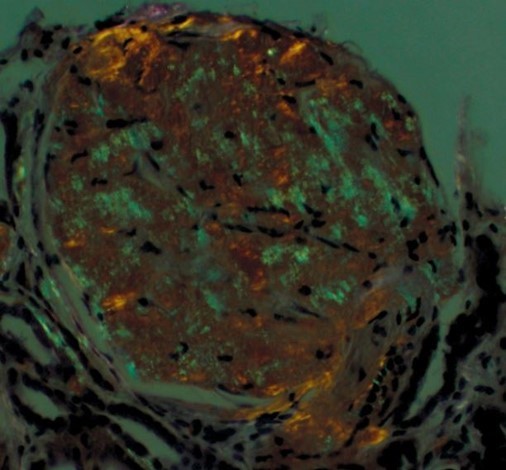

What is this and why?

Amyloidosis, due to the Congo Red stain showing apple-green birefringence on polarized light